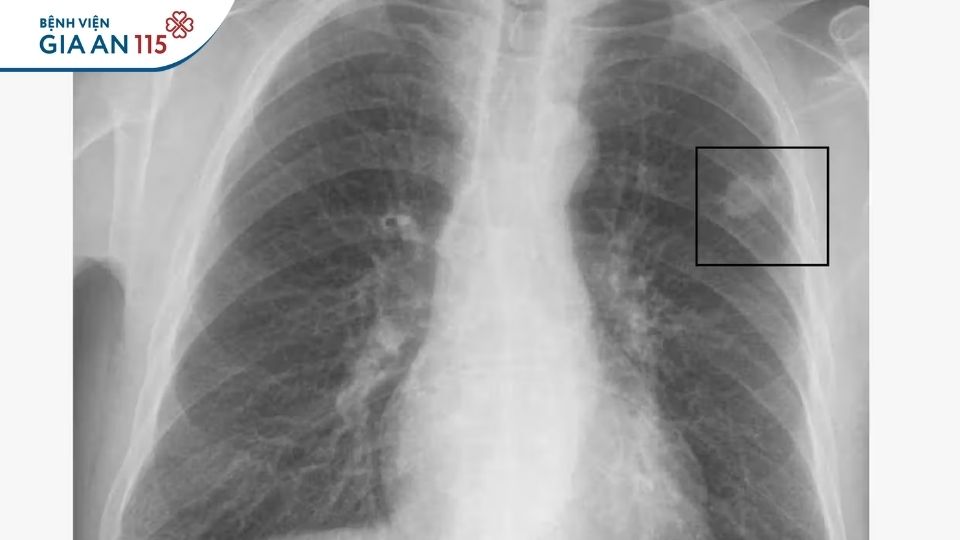

Trên hình ảnh ban đầu, tổn thương có thể khó phân biệt hoàn toàn với u ác tính (Ảnh minh họa)

U phổi là thuật ngữ chung chỉ một khối mô phát triển bất thường trong nhu mô phổi. Trên hình ảnh học, tổn thương này có thể được mô tả là “nốt phổi”, “khối phổi” hoặc “tổn thương choán chỗ”.

U phổi lành tính là những khối tăng sinh bất thường của tế bào trong phổi nhưng không xâm lấn mô lân cận, phá hủy cấu trúc phổi hoặc di căn đến cơ quan khác. Tuy được xếp vào nhóm “ít nguy hiểm hơn”, u phổi lành tính vẫn cần được đánh giá cẩn thận vì trên hình ảnh ban đầu, một số tổn thương có thể khó phân biệt hoàn toàn với u ác tính.